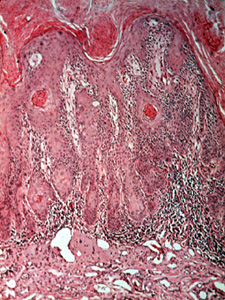

Las cortes microscópicas de la queilitis actínica muestra  mucha queratina en la superficie

Con alargamiento de la basal formando lomas y debajo se observs el tejido conjuntivo inflamado